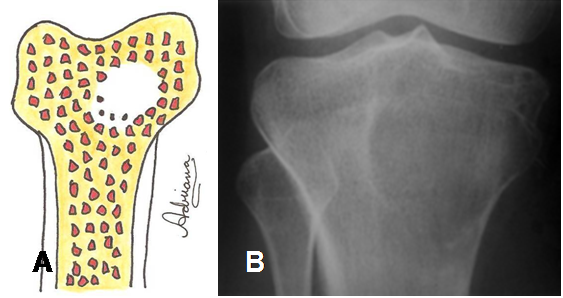

Fig 28. Lesión geográfica tipo 1C.

A: Diagrama de lesión de bordes parcialmente definidos.

B: Rx AP. Imagen de bordes parcialmente definidos, que corresponde a tumor de células gigantes.